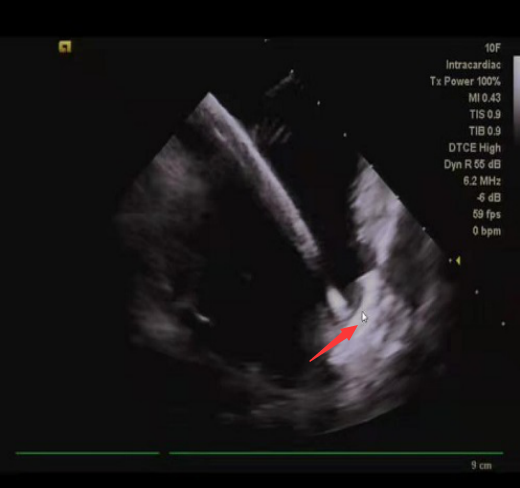

术中,张志辉教授带领罗文治主治医师及邓煦主治医师,首先对病人进行房颤的环肺静脉电隔离及左心房基质改良,随后应用心腔内超声,对患者的左心耳形态及直径大小进行了精确测量,结合X线下造影的影像,使用了ACP20mm的左心耳封堵器对患者左心耳进行封堵,封堵器到位顺利,一次性展开成形,再次应用腔内超声对展开后的封堵器进行测量,封堵器完美封堵左心耳开口,且对左心耳附近的结构没有影响,遂释放封堵器。整个手术过程患者均在清醒状态下,术中患者各项生命体征平稳。

心腔内超声下左心耳封堵器(箭头所指)